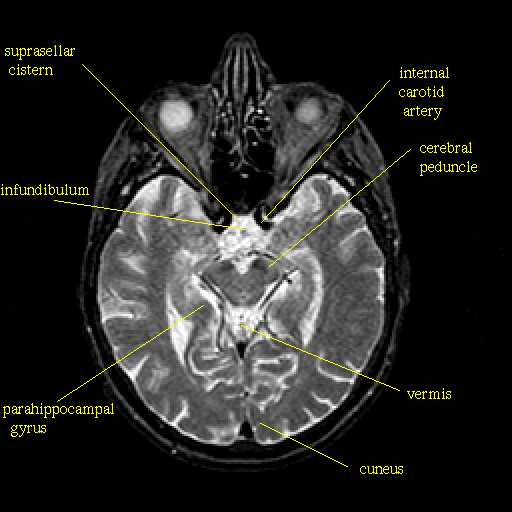

T2-weighted structural MR: Slice 22

Slice 22